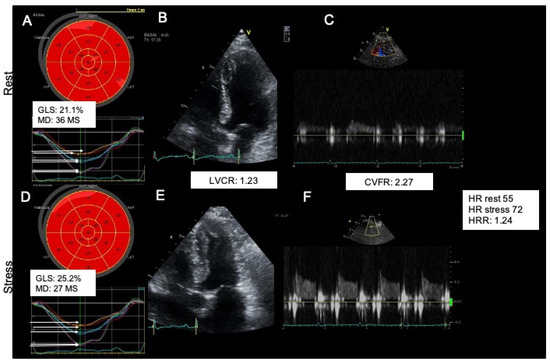

| GLS (%) | 22.9 ± 3.8 | 21 ± 4.5 | 23.6 ± 3.3 | 0.007 |

| MD (ms) | 45.2 ± 17.7 | 53.9 ± 15 | 41.9 ± 17.6 | 0.0005 |

| LV contractile reserve | 1.33 ± 0.42 | 1.33 ± 0.4 | 1.33 ± 0.43 | 0.844 |

| LV Synchrony Delta | 6 (4.7–16) | 3 (−8–8.1) | 7 (−1–18.8) | 0.035 |

| Strain Stress-Rest Delta | 2.9 (0.6–4.8) | 0.4 (−2–3.4) | 3.3 (1–3–5.3) | <0.0001 |

| Strain Reserve | 1.14 ± 0.16 | 1.01 (0.91–1.16) | 1.17 (1.06–1.28) | <0.0001 |